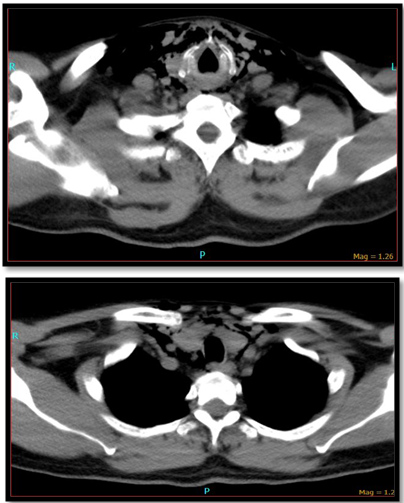

The second patient is a 58year male who came to the emergency room with alleged history of RTA following which he developed difficulty in swallowing and spitting out blood stained sputum. Examination revealed subcutaneous emphysema and tenderness over the laryngeal frame work. CT-neck plain showed extensive emphysema of neck with extension into the superior mediastinum (Figure 1) and fracture of thyroid cartilage at the midline with mild lateral displacement of the right side ala (Figure 2). He was admitted in the intensive care unit and was monitored for 24hours after which tracheostomy followed by neck exploration and laryngeal stabilization under general anesthesia was performed where in the fragmented thyroid cartilages were sutured. He was on ryles tube feed for 2months following which he was decannulated and ryles tube was removed.

Figure 7CT- Neck showed extensive subcutaneous emphysema with extension into posterior pharyngeal space and left posterior neck space.